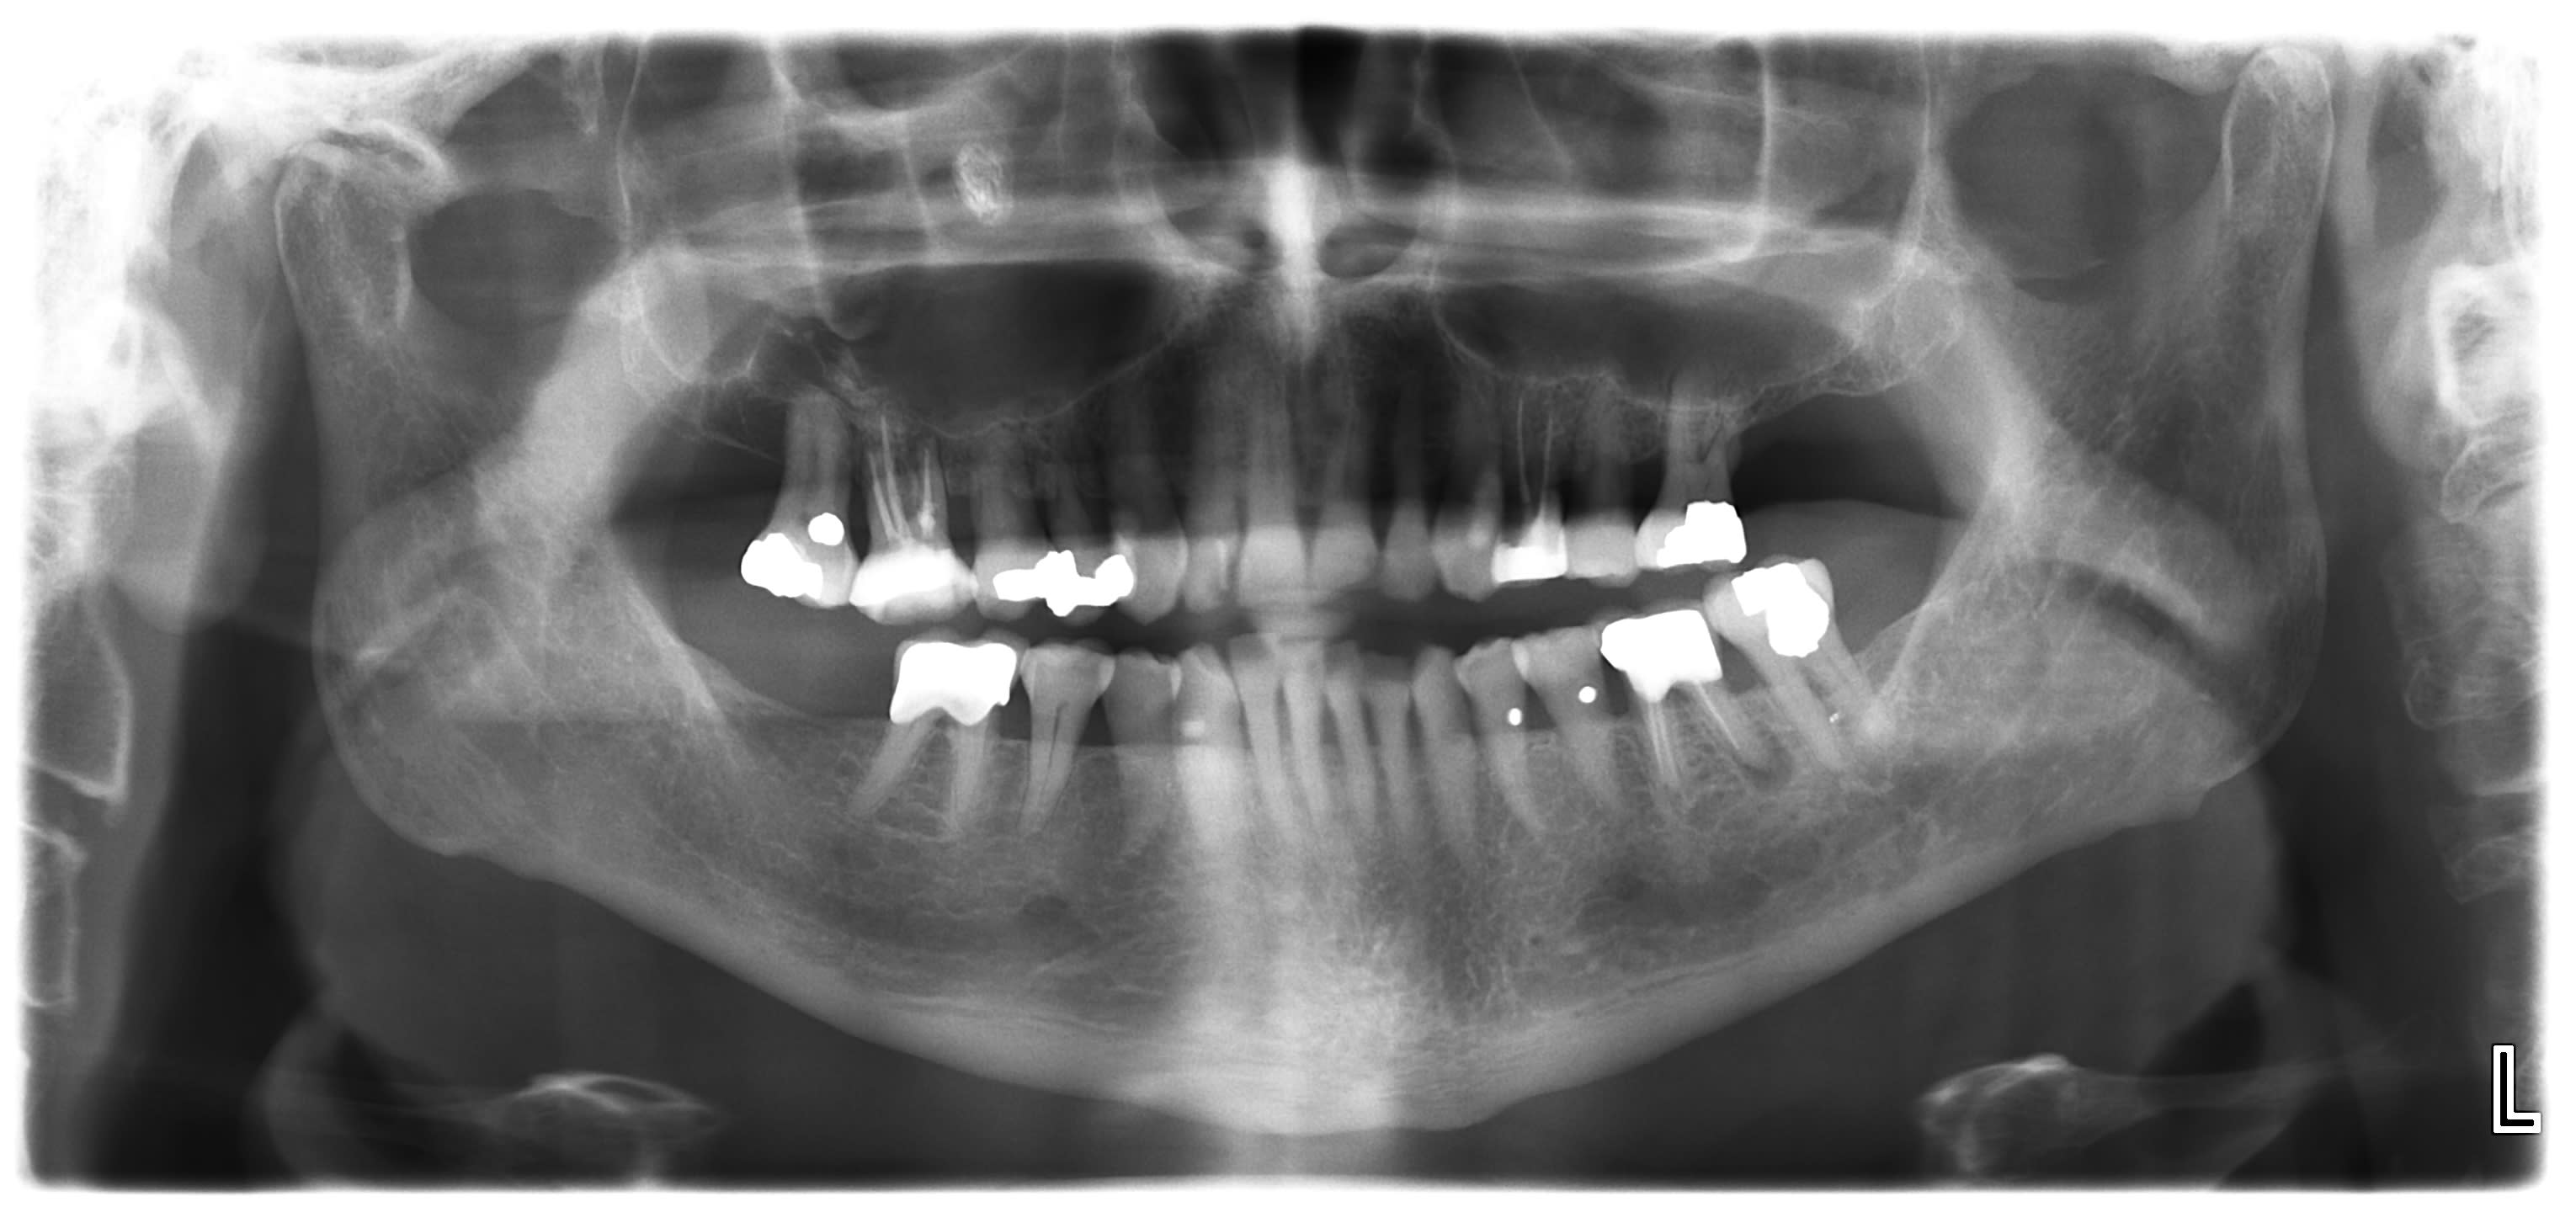

Patient de 75 ans, pas douleurs speciales. Nez bouche cote droit.

Diagnostic?

vu qu'il y a un truc plus radio opaque dans le sinus.....aspergillose?

Yes, aspergillose. retiree ce matin... C est pas beau a voir, dommage j ai pas pris de photo. C est la semaine du sinus. Une sagesse, une aspergillose et demain j ai un apex a aller chercher... :0))

et d'ailleurs si rien n'est fait, y a aussi la 36 qui va disparaître :)